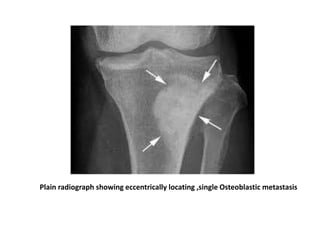

Plain radiograph showing eccentrically locating ,single Osteoblastic metastasis

Plain radiograph showingeccentrically locating ,single Osteoblastic metastasis